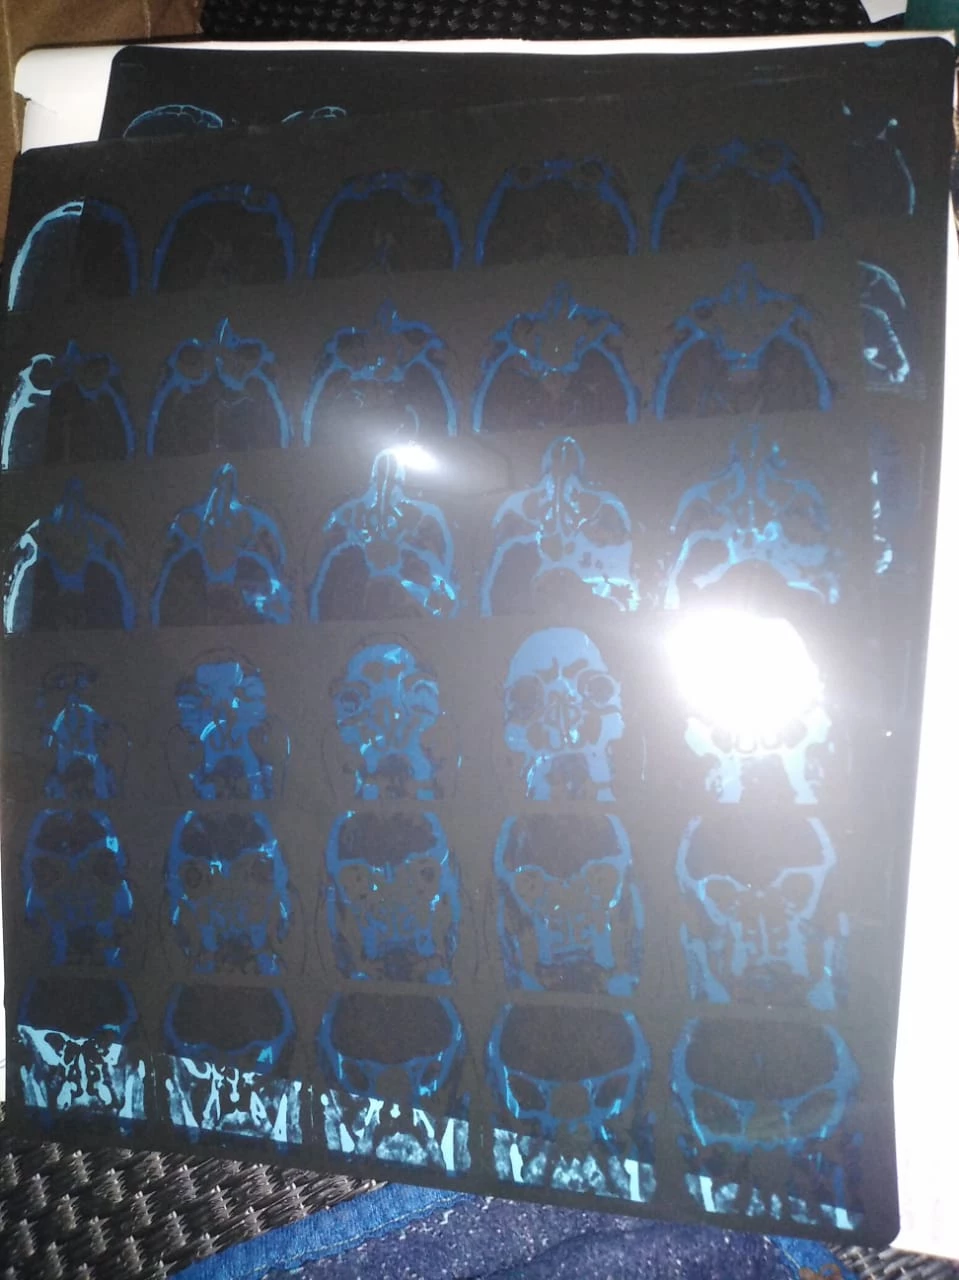

Cada vez necesita más análisis médicos, radiografías y escáneres. Estos procedimientos son muy costosos en Marruecos y Ali ya no puede asumir todos estos gastos.

• Radiografías y escáneres necesarios para su diagnóstico.